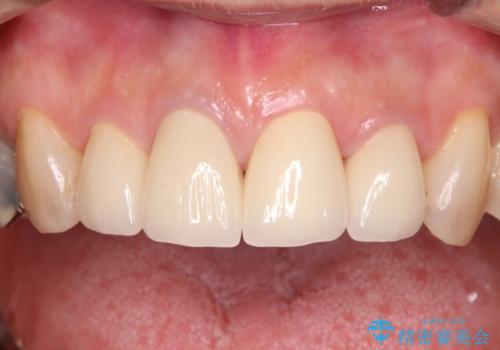

インプラントあるいはブリッジによる補綴治療が考えられましたが、前後の歯が大きな銀歯であったため、オールセラミックブリッジにより3本の歯を審美的に仕上げることとしました。

奥歯の治療をしている間に前歯の治療をどのように勧めるのか検討していただき、最終的には4歯を一度に治療し、審美的に仕上げることとしました。